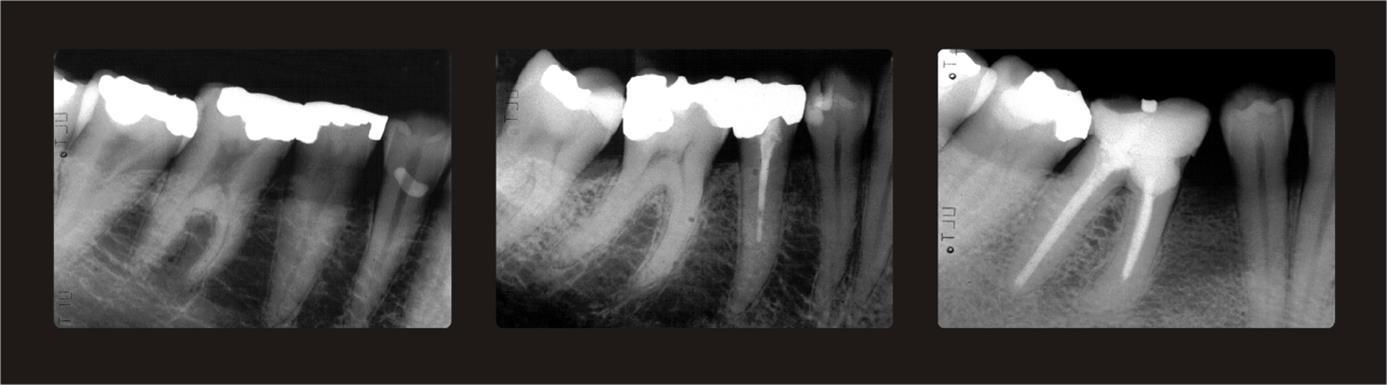

Three periapical and three panoramic radiographs with varying degrees of trabeculation were used as index references to assess the trabeculation pattern as proposed by Lindh et al. in 199611 and modified by Jonasson et al. 2001.4 The periapical radiographs are shown in Figure 1. Periapical radiographs are more easily interpreted than panoramic radiographs, which demand training (Pham et al 2010).12 With the help of these radiographs, the trabeculation of the mandibular alveolar process was classified as either sparse (regarded as an ordinal variable with the value 1), mixed dense and sparse trabeculation (value 2) or dense (value 3). Sparse trabeculation had large intertrabecular spaces apparent in most of the alveolar processes, particularly in the crestal dentate premolar area. Dense trabeculation had small intertrabecular spaces everywhere. Mixed dense and sparse trabeculation was dense crestally and sparser apically. In the event of uncertainty, the mixed category was chosen (Figure 1).

Figure 1.Periapical reference radiographs.Left: Sparse trabeculation with large intertrabecular spaces and almost invisible trabeculae. Middle: Mixed dense and sparse trabeculation with small intertrabecular spaces cervically and larger spaces more apically. Right: Dense trabeculation with small intertrabecular spaces.

Periapical reference radiographs.Left: Sparse trabeculation with large intertrabecular spaces and almost invisible trabeculae. Middle: Mixed dense and sparse trabeculation with small intertrabecular spaces cervically and larger spaces more apically. Right: Dense trabeculation with small intertrabecular spaces.